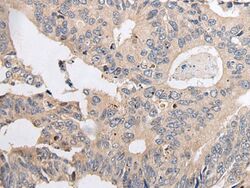

- Immunohistochemical analysis of ARL5A in paraffin-embedded Human colorectal cancer tissue using (left) ARL5A Polyclonal Antibody (Product # PA5-67615) at a 1:20 dilution and (right) is treated with synthetic peptide. (Original magnification: x200).